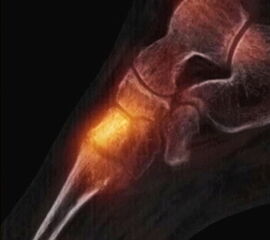

Abbildung 2.1.

Bildbeispiele symptomatische OCL

Zum Lesen der Bildbeschreibung und zur Vollansicht bitte das Bild anklicken. Bild: H. C. Rischke

Abbildung 2.2.

Bilder eines Patienten mit Z. n. mehrfachen Sprunggelenksdistorsionen in der Vergangenheit, besonders heftige Distorsion des linken Sprunggelenkes 5 Wochen vor der Untersuchung. Die SPECT/CT zeigt eine instabile osteochondrale Läsion mit deutlicher Aktivierung.

Abbildung 2.3.

Klärung bei Schmerzen im rechten OSG bei OCL an der medialen Talusschulter. Z. n. OSG-Distorsion vor 2 Jahren und Z. n. OSG-Fraktur / Syndesomosenruptur. Ausgedehnte OCL, hier jedoch kein erhöhter Knochenmetabolismus; lediglich Nachweis einer Stressreaktion im Bereich der Synchondrose eines Os trigonum als Schmerzursache.